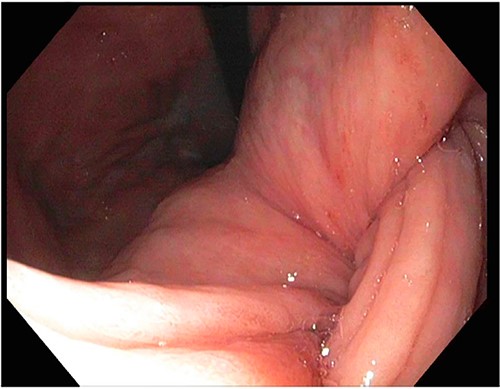

A 72-year-old patient with no past surgical history and a past medical history of developmental delay, hypertension and hyperlipidemia presented to the Emergency Department in mild distress with periumbilical abdominal pain, nausea and intractable vomiting for 1 day. The patient denied any hematemesis, bowel changes, fever, melena or hematochezia. On physical exam, the abdomen was unremarkable, and a computed tomography (CT) scan with contrast of abdomen and pelvis revealed a 5.6 × 5.3 cm heterogeneous mass arising from the body of the stomach extending into pylorus with no evidence of bowel obstruction and liver metastasis (Fig. 1). Subsequently, esophagogastroduodenoscopy (EGD) showed a large, fungating and ulcerated mass and it was reported to involve two-thirds of the luminal circumference in the gastric body (Fig. 2). Cold forceps biopsy showed gastric mucosa with hyperplastic changes, mild chronic active antral gastritis with focal intestinal metaplasia, negative for Helicobacter Pylori and dysplasia. Surgical management was discussed with the family, but they refused any surgical intervention.

A large fungating gastric mass arising from the body of the stomach on endoscopy.

After a few days, the patient was found to have a large volume of melenic stool. A CT angiogram of the chest, abdomen and pelvis was done, revealing a mass in the antrum and pylorus of the stomach with a portion of the stomach pulled into it, consistent with gastroduodenal intussusception without any active extravasation. Repeat EGD showed a large, fungating, pedunculated mass with no bleeding and no stigmata of recent bleeding in the gastric body (Figs. 3 and4) and confirmed gastroduodenal intussusception. The intussusception spontaneously reduced while attempting to push passed the mass. The mass was too large to resect endoscopically. Given these new findings, the family agreed to surgical intervention. An exploratory laparotomy was made, and the patient underwent partial gastrectomy, distal antrectomy and Billroth II procedure. The resected large gastric body mass within the mid gastric body and two nodes were sent for frozen section and immunohistochemical analysis. The pathology report confirmed the mass as a GIST, spindle cell type with no significant nuclear atypia or mitosis, arising from muscularis propria, without mucosal invasion and R0 margins. The neoplastic cells stained positive for CD117 (KIT), CD34 and Desmin (focally). The tumor was T3N0M0 with a low mitotic rate, histologic grade G1 and was deemed low risk (3.6%). The patient was discharged to a subacute rehab with an uneventful recovery.